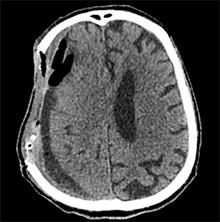

53 m. vyras sumuštas gatvėje ir greitosios medicinos pagalbos atvežtas į Priėmimo skyrių. Pacientui atlikta galvos kompiuterinė tomografija (GKT). Rasta: poūmė, stora, apie 16 mm dydžio subdurinė hematoma (SDH) dešinėje pusėje konveksitaliai ir ūmi nedidelė SDH kairėje pusėje frontoparietaliai. Vidurio struktūrų dislokacija (VSD) į kairę – minimali. Kairėje – kaukolės skliauto linijinis lūžis. Nustatyta nosies kaulų, nosies pertvaros, dešiniojo viršutinio žandikaulio kaktinės ataugos ir kūno, sinuso sienelių lūžių, dešinės akiduobės medialinio krašto lūžių ir dešiniojo skruostinio lanko lūžių (1 pav.). 2020 m. liepos mėn. pacientas skubos tvarka operuotas: atlikta dešinė kraniotomija, pašalinta hematoma. Atlikus kontrolinę GKT, buvo matyti, kad pašalinta didžioji hematomos dalis (2 pav.). Pacientas konsultuotas veido ir žandikaulio chirurgo, skubus chirurginis gydymas neindikuotas. Praėjus 3 savaitėms, pacientas, esant gerai funkcinei ir neurologinei būklei, tolesnio gydymo perkeltas į slaugos ligoninę, vėliau išleistas gydytis ambulatoriškai.

2 pav. Po pirmosios operacijos (didžioji hematomos dalis pašalinta, VSD be dislokacijos)